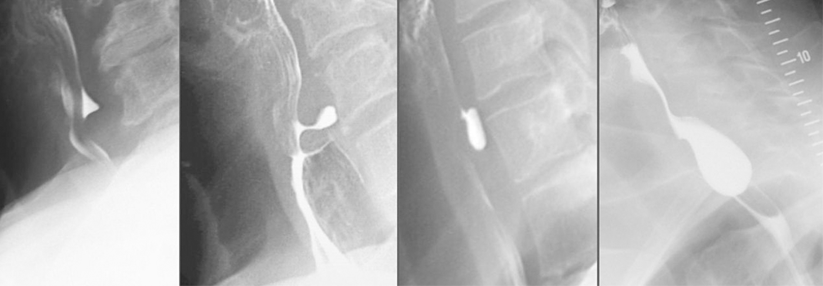

Ein Zenker-Divertikel muss operiert werden. Doch welches Verfahren eignet sich? Ein flexibel endoskopischer Eingriff bietet zwar den Vorteil der…